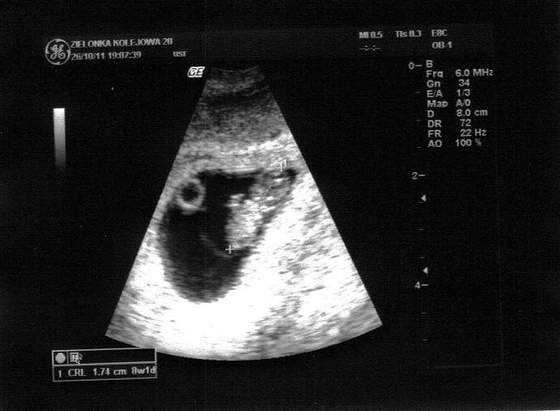

ja jednak potwierdzam ze wszystko w zaleznosci od sprzetu jaki maja, juz w 5 tyg widzialam wiecej i wyrazniej niz dzisiaj. ale najwazniejsze ze sobie tam maluszek zyje:)))

8t0d, 14mm

Wszystkie maluszki są superanckie ,a jakość fotki po prostu zależy od sprzętu, mi lekarz powiedział że to ostatnie zdjęcie kiedy maluszek mieści się cały w kadrze , a sprzęt ma pewnie dobry bo będzie robił mi usg genetyczne w cenie wizyty z czego się cieszę bo chodzę do niego 6 lat i mu ufam:)

No to ja wkleję aktualne foto. Teraz mamy już 8tyg i 1dzień. I już 17mm, a 2tygodnie temu było tylko 2,8mm. Szoook jak te maluchy rosną :). Jak się dobrze przyjrzycie, to już rączkę widać. I serducha słuchaliśmy :)